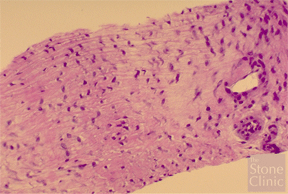

The biopsy was obtained from the superior to inferior surface. The photo of the biopsy on the right demonstrates the cellular migration of the meniscal fibrochondrocytes (cartilage cells of the kind that produce fibrocartilage rather than pure hyaline cartilage) into the collagen meniscus implant, demonstrating that it worked effectively as a regeneration template.